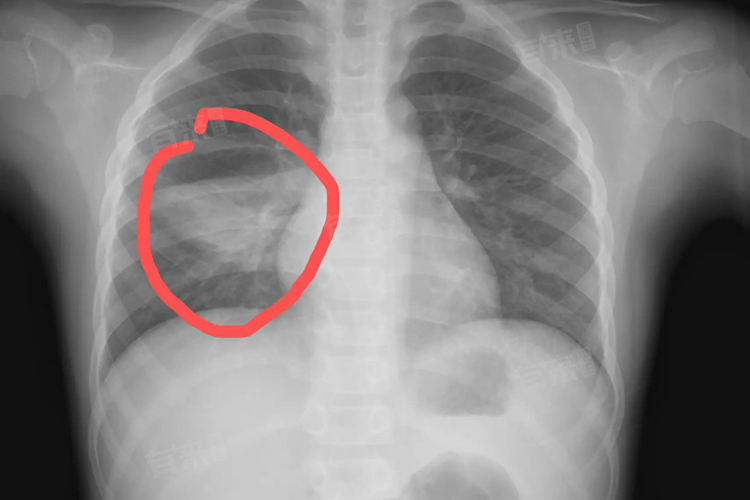

- 然而,在病情较重的情况下,儿童肺炎需要住院治疗。例如,当儿童出现高热不退、剧烈咳嗽、呼吸困难、口唇青紫、发绀等症状,或者影像学检查提示合并肺实变、肺不张、胸腔积液等特殊情况时,必须住院治疗。因为重症肺炎可能会引起心力衰竭、肺炎脑病等并发症,甚至危及生命。住院治疗可以方便医生随时监测儿童的体温、呼吸、心率等生命体征,并根据病情变化及时调整治疗方案。